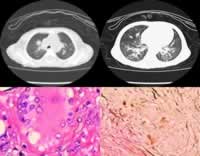

正常肝臟中此酶的活力最高,肝、腎、腦、小腸亦富於此種酶。此病患者的肝、脾等組織中酶的活力降低至50%以下。患兒全身網狀內皮系統中可查見富含脂類的直徑為20~90μm的大型泡沫細胞,以脾、骨髓、肝、肺和淋巴結等部位為主。這種泡沫細胞又稱為尼曼-匹克細胞,通常僅見一個偏位的小細胞核,染色質疏鬆;胞漿充滿脂類小滴(胞質體),在未染色片上呈“桑葚”狀,Giemsa染色時,胞漿呈藍或藍綠色,內有深淺不一的藍色顆粒。不同於Gaucher細胞的是:酸性磷酸酶染色呈弱陽性;Schultz反應(檢測膽固醇)呈陽性。亦可用位相顯微鏡或電鏡檢查鑑別兩者。

尼曼匹克氏病2、骨髓象含有典型的尼慢-匹克細胞,常稱泡沫細胞,核細胞直徑20~100μm;核較小,圓形或卵圓形,一般為單個,也可有雙核;胞漿豐富,充滿圓滴狀透明小泡,類似桑椹狀或泡沫狀。電鏡下顯示小泡周圍有部分膜層結構環繞。用位相顯微鏡對未染色標本作檢查,可顯示細胞漿內呈小泡泡狀,與高雪細胞不同。在偏光下觀察,小泡呈雙折射性;在紫外線下螢光呈綠黃爭。生化特點PAS反應弱陽性,胞漿內的小泡壁呈陽性,小泡中心陰性;酸性磷酸酶、鹼性磷酸酶、蘇丹黑均呈陰性反應。

6、X線檢查:無特徵性X線表現,在長期存活病例,由於充脂性組織細胞在骨骼內大量增殖可表現骨質疏鬆、髓腔增寬、骨皮質變薄,甚至長骨可出現局灶性破壞區,但無骨骼膨大畸形改變。嬰兒期以後肺泡受充脂性組織細胞浸潤,肺部可見類似組織細胞增生X症的表現。總之無特異性,僅提供輔助診斷的依據。